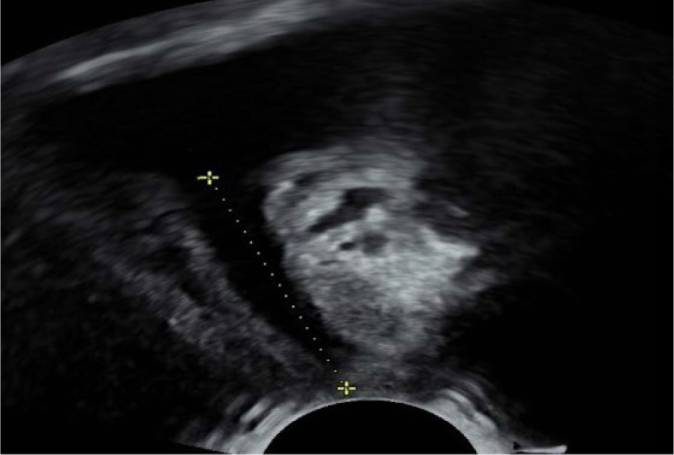

目的:本研究旨在探讨尿动力学检查中观察到的特定尿道功能参数与盆底超声评估的部分尿道特征之间的相关性。此外,我们还对因压力性尿失禁而接受外科治疗的女性患者进行了评估。材料与方法:对192例女性患者行无耻骨后张力阴道胶带手术治疗应激性尿失禁进行回顾性研究。在静息剖面术中评估最大尿道闭合压力和功能尿道长度。超声测量,连同漏斗的评估,作为盆底检查的一部分,按照Kociszewski描述的技术进行。有临床意义的盆腔器官脱垂、前房室手术史、既往放疗或膀胱过度活动症状的患者被排除在分析之外。结果:对尿动力学和超声检查结果进行统计学评价。所分析的尿动力学和超声参数之间没有相关性。在所有被评估为适合放置无张力阴道胶带的压力性尿失禁患者中,证实了长尿道漏斗。结论:结果表明尿动力学检查和超声检查评估尿道解剖和功能的不同方面,因此它们的结果不能互换使用。所有临床和尿动力学证实的压力性尿失禁患者在盆底超声检查中均发现长尿道漏斗。

Aim: This study aimed to examine the correlations between specific urethral function parameters observed in urodynamic testing and selected urethral characteristics evaluated by pelvic floor ultrasonography. Additionally, the presence of urethral funneling during straining was evaluated in female patients referred for surgical treatment of stress urinary incontinence.

Material and methods: A retrospective study was conducted on 192 female patients referred for surgical treatment of stress urinary incontinence with the use of retropubic tension-free vaginal tape. Maximum urethral closure pressure and functional urethral length were evaluated urodynamically during resting profilometry. Ultrasound measurements, along with the assessment of funneling, were performed as part of the pelvic floor examination, following the technique described by Kociszewski. Patients with clinically significant pelvic organ prolapse, a history of anterior compartment surgery, prior radiotherapy, or symptoms of overactive bladder were excluded from the analysis.

Results: The values obtained from urodynamic and ultrasound examinations were evaluated statistically. No correlation was identified between the analyzed urodynamic and ultrasound parameters. Long urethral funneling was confirmed in all patients with stress urinary incontinence assessed as eligible for the placement of tension-free vaginal tape.

Conclusions: The results indicate that urodynamic and ultrasound examinations assess distinct aspects of urethral anatomy and function, and therefore their findings cannot be used interchangeably. Long urethral funneling assessed during pelvic floor ultrasonography was noted in all patients with clinically and urodynamically confirmed stress urinary incontinence.